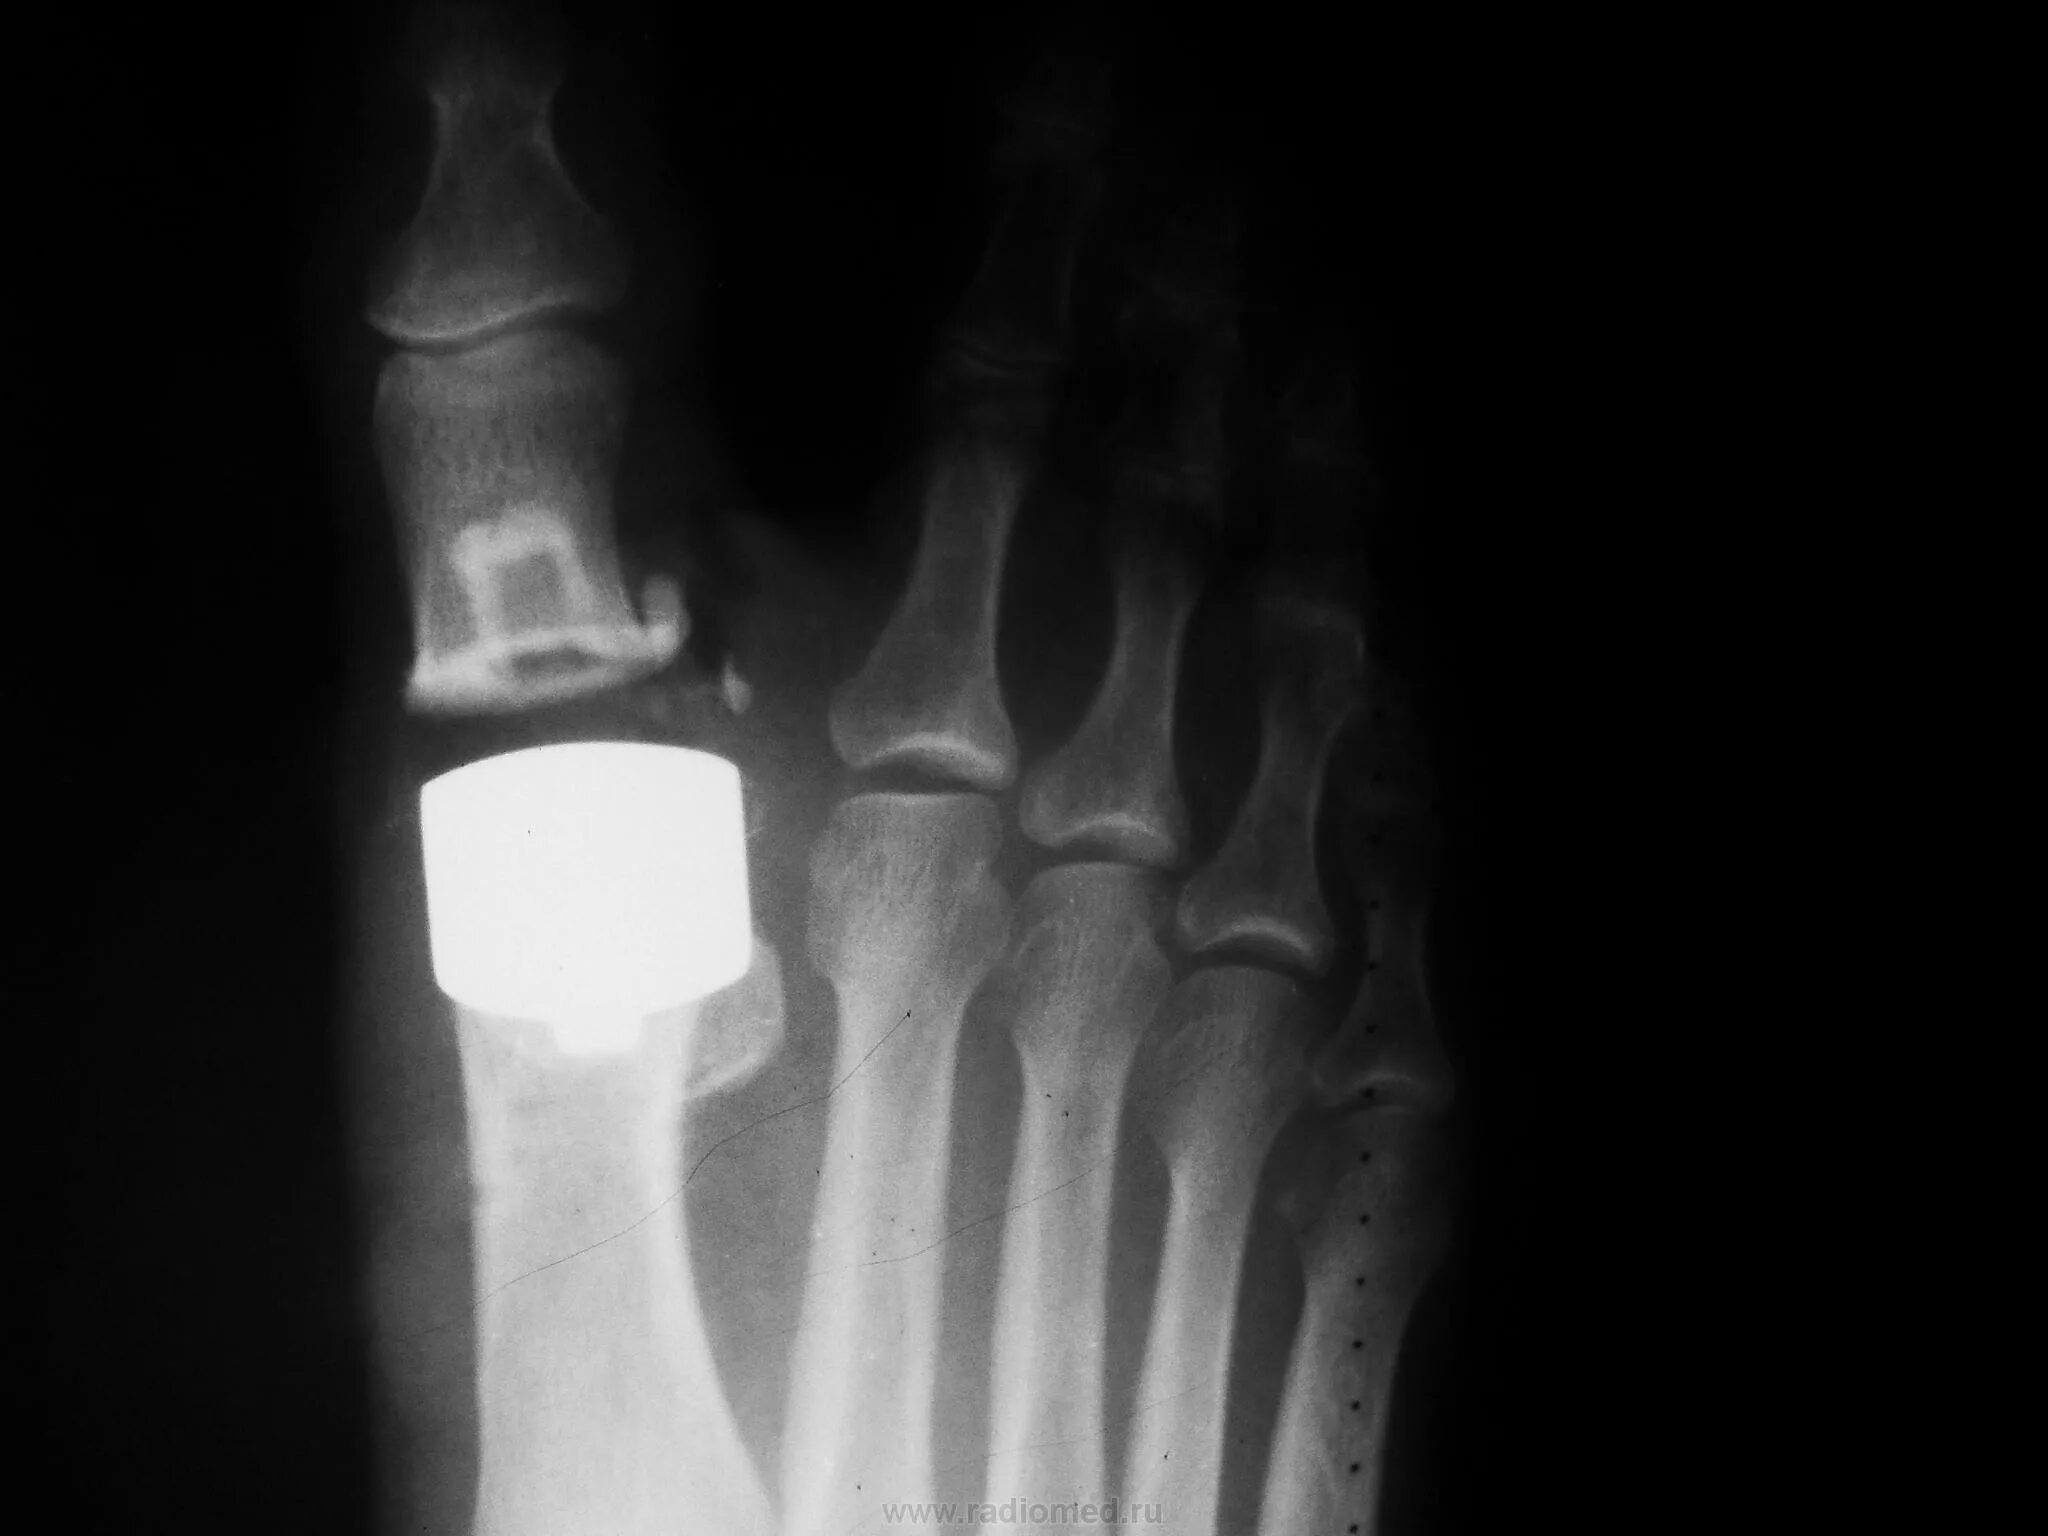

Артроз 1 степени плюснефалангового сустава стопы